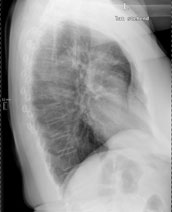

Eine 69-jährige Patientin klagt über einen seit mehr als 4 Wochen anhaltenden Husten mit wenig Auswurf. Die Frage nach Dyspnoe wird verneint. Fieber besteht keines.

Die körperliche Untersuchung ist unergiebig. Der behandelnde Arzt hat aufgrund der Raucheranamnese und des nicht enden wollenden Hustens ein Röntgenbild gemacht:

Thorax seitlich

Welche Befunde fallen auf (mehrere richtige Antworten möglich)?

Wie beurteilen Sie nun das Röntgenbild?